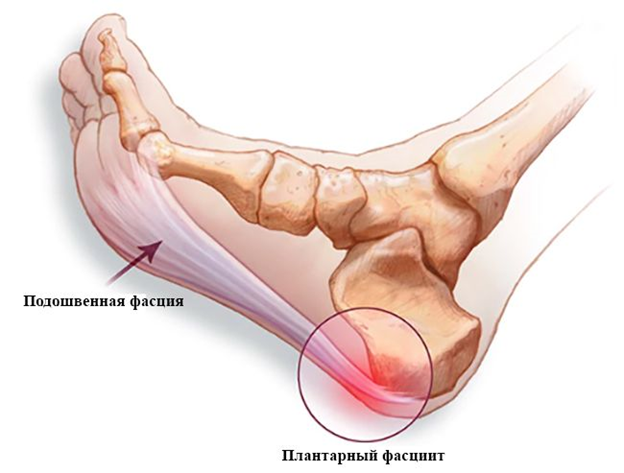

Данное состояние называется плантарный фасцит. Это интенсивные боли в стопе, чаще в пятке, а при длительном течении это состояние может привести к пяточной шпоре. Сейчас расскажу, что это такое, почему это происходит и что с этим делать.

По низу стопы от пятки к головкам плюсневых костей и основным фалангам идет толстая широкая жила, которая называется подошвенной, или плантарной, фасцией. Эта фасция отмечает за пассивную стабилизацию продольного свода – той ямки на стопе, в которую в кроссовке упирается супинатор. Стабилизация фасцией похожа на тетиву лука.

Свод держится за счет разницы в длине дуги продольного свода и длины фасции (фасция короче и поэтому выгибает продольный свод). Это очень упрощенная модель, не учитывающая другие связки стопы, мышцы, а также наличия в стопе суставов и костей разного размера и формы, но для понимания происхождения плантарного фасцита/пяточной шпоры эта модель достаточна.

По время шага плантарная фасция испытывает продольное растяжение (лук пытается выпрямиться), что может привести ее к разрывам в точках крепления. В здоровой стопе разрывы не происходят благодаря динамической стабилизации стопы мышцами. НО, если у человека есть проблемы с мышцами стопы из-за плоскостопия, долгой ходьбы, многочисленных перегрузок или неврологических нарушений, то плантарная фасция может частично разорваться.

Пока стопа отдыхает без нагрузки в месте разрыва или разрывов начинают формироваться нежные рубцы, которые легко рвутся при интенсивной нагрузке. Поэтому мы и испытываем боли после ночного отдыха или после того, как долго посидим, а потом резко встанем.

А почему формируется подошвенная шпора? Фасция все время тянет за свою точку крепления к кости, точнее она тянет надкостницу, покрывающую данную кость. При раздражении надкостница начинает стимулировать образование костной ткани, и мы получаем картину гребешка, или шпоры, на рентгенографии.

Иногда шпора выглядит как что-то издали напоминающее кость, иногда шпора перестраивается в истинную кость, но для понимания процесса это не критично. Иногда шпора бывает настолько массивной, что может даже произойти ее перелом.

Теперь мы немного разобрались с тем, как возникает плантарный фасцит, т.е. воспаление подошвенной фасции, а за ней и пяточная шпора. Но что с лечением?